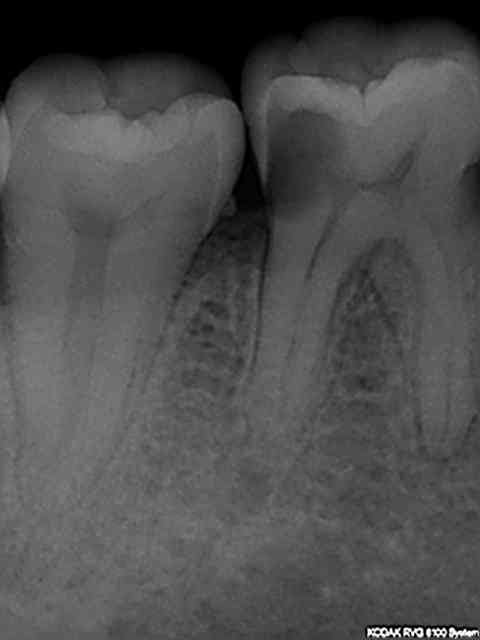

Nouvelle Patiente Mrs X présentant des signes d'appels simultanés sur 36 46. Suspicion d'atteinte pulpaire donc 2 rétro alvéolaires gratuites.-))

Diagnostic : pulpite sur 46 et 4 eme ° sur 36.

Dans le souci de ne pas irradier la patiente inutilement aucune autre radiographie gratuite d'un autre secteur n'est réalisée. Qui plus est le docteur chicot 29 étant équipé d'un capteur kodak 6100 ne peut pas réaliser de mordus rétro coronaires. Le Dr chicot 29 ayant une demi-heure devant lui réalise l'endo de 46 et cote donc Z6 fois 2 + SC 34 et met la patiente sous atb pour le 4 eme de la 36. Ce faisant il fait économiser à la caisse une C à 23 euros.-))

Meme en mode Bw rétro coronaire (capteur horizontal) il est impossible d'avoir toutes les molaires et prémolaires avec un kodak 6100 meme avec 4 clichés (Je ne comprend pas d'ailleurs le capteur semble couvrir toutes les dents) Il manque la 7 ou la 4. 8 clichés sont donc nécessaires (contre 12 en rétro alvéolaires capteur vertical).

Une rétro alvéolaire a été réalisé en sus pour la 37 bien qu'elle ne présente pas de "signes d'appels". Une magnifique endo révélée comme d'hab, le patient est éclairé quant à la survenue d'un éventuel problème. On peut se poser des questions également sur la pertinence des micro classes 1 amalgame sur 46 et 47 a moins que ce soit la conséquence d'un comportement "imaginatif " cher à Catherine M pour rentabiliser les soins opposables.